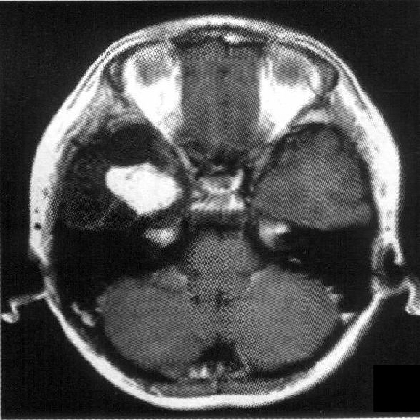

标题: PED1818:男,13岁。头痛5天,复视、呕吐3天。体检:神经生 [打印本页]

标题: PED1818:男,13岁。头痛5天,复视、呕吐3天。体检:神经生

右中颅窝见囊性占位影,其中央见块状高密度影,高密度块后后缘见条状钙化?前部与殘存颞叶皮质相连,临近骨质无异常,病灶囊变区呈长t1长t信号,实性区呈中等信号,增强(最后两副是增强t1像吧)有明显强化,实性块影上部尚见鸟嘴状影(比较像脑膜尾),考虑右中颅窝脑膜瘤可能性大,不排除室管膜瘤,畸胎瘤等

病理:囊性脑膜瘤